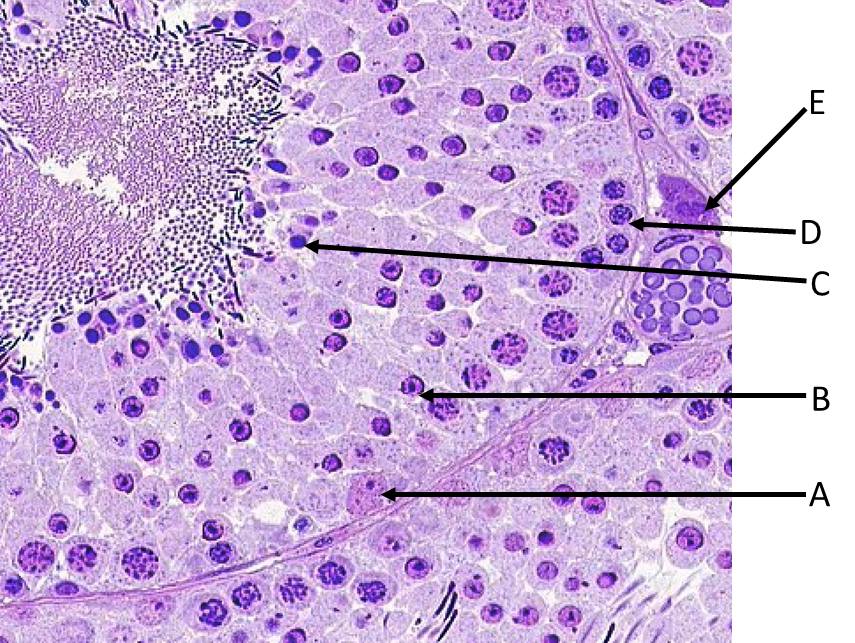

Which cell type shown would have the most abundant receptors for luteinizing hormone (LH)?

A. A

B. B

C. C

D. D

E. E

B.

Which of the labeled cells is a stem cell for sperm production?

A. A

B. B

C. C

D. D

E. E

D. D

Which of the labeled cells secretes androgen binding protein involved in sperm maturation?

A. A

B. B

C. C

D. D

E. E

A.A